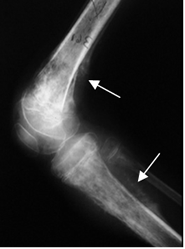

Fig 69. Osteosarcoma.

Rx lateral. Reacción perióstica en peine en la parte posterior del fémur, por osteosarcoma parosteal.